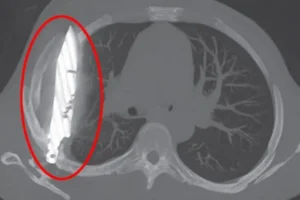

Mjekët, të habitur nga ky rast, vendosën të kryejnë një radiografi.

Rezultati ishte shokues: një thikë e madhe ishte ngulur në kraharorin e tij, duke kaluar përmes shpatullës së djathtë dhe duke shmangur organet kryesore.Ky zbulim i papritur ka nxitur diskutime mbi rëndësinë e kontrollit të rregullt shëndetësor dhe diagnostikimin e saktë.

Mjekët shpjeguan se thika kishte shkaktuar vetëm një infeksion të lehtë, duke e mbajtur pacientin në një gjendje të dukshme shëndetësore për një periudhë të gjatë.Pas operacionit për heqjen e thikës dhe pastrimin e indit të vdekur, pacienti u shërua plotësisht.